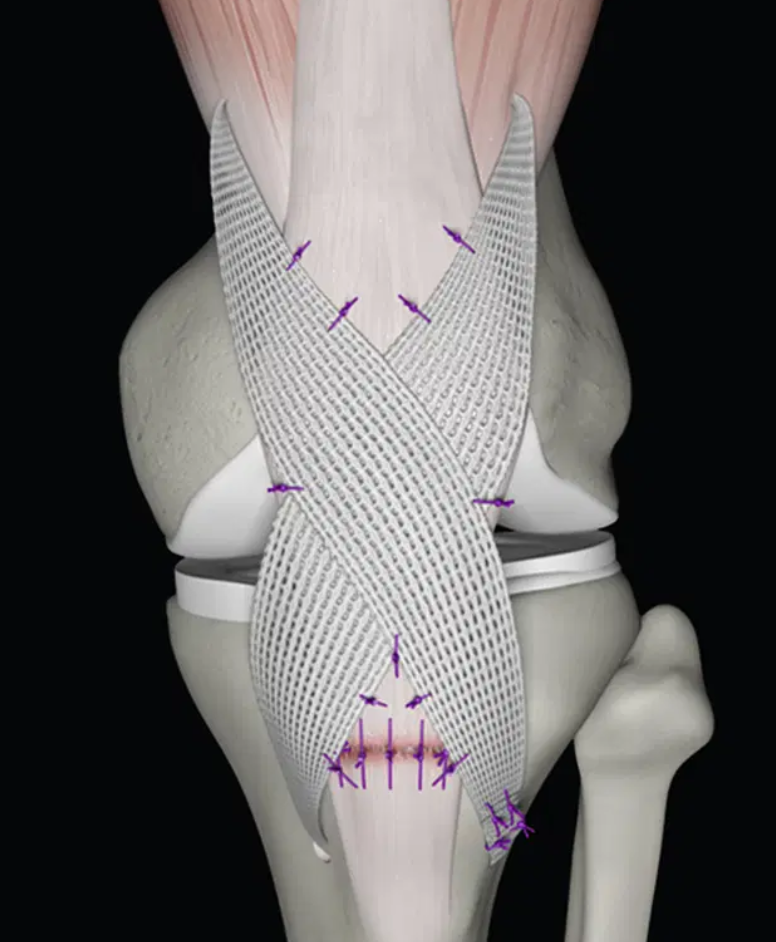

Gân nhân tạo tái tạo dây chằng Poly-Tape các cỡ

Dùng trong phẫu thuật tái tạo gân cơ tứ đầu đùi, gân bánh chè, MPFL, … Cung cấp độ bền nội tại tuyệt vời và giúp việc phục hồi chức năng vận động diễn ra sớm hơn. Cấu trúc: Băng dệt hở với các đoạn dệt dày, thuôn thành sợi ở mỗi đầu. Cấu trúc này cho phép mô tự nhiên phát triển tích hợp vào trong thiết bị.

Tiêu chuẩn: CE, ISO